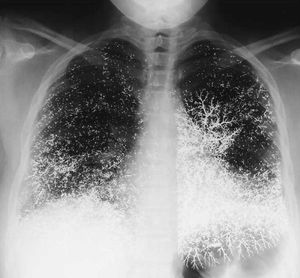

This is what happened to a patient when 10ml of elemental mercury what injected into them. What should they do?